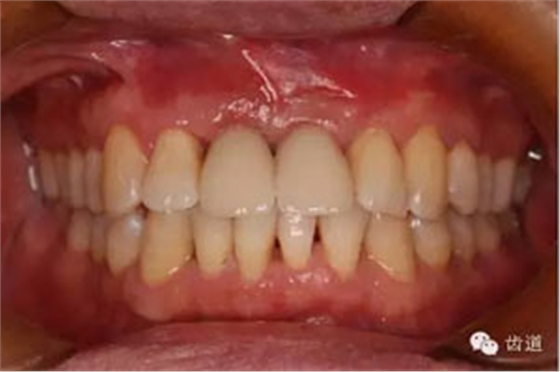

臨床檢查:

患者高位笑線,薄牙齦型。

11,21缺失。因外傷,導(dǎo)致11骨高度降低。